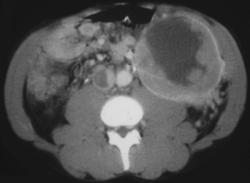

Diagnosis

Gastritis